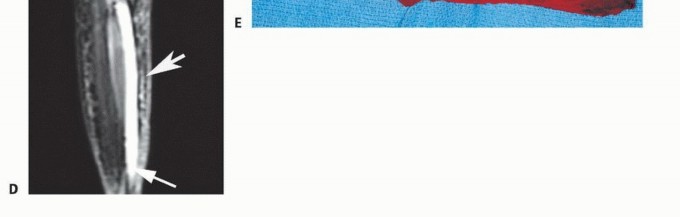

الوصول إلى العضلة النعلية: يتم تحقيق التعرض لاستئصال العضلة النعلية عن طريق قطع وتر أخيل جزئيًا أو كليًا، ورفع رؤوس عضلة الساق الإنسية والوحشية نحو الأعلى.

فصل واستئصال العضلة النعلية: عن طريق التشريح غير الحاد، تُفصل العضلة النعلية عن الحاجز العضلي المستعرض الذي يحدد الحجرة الخلفية العميقة. ثم يمكن فصل العضلة النعلية عن منشئها الظنبوبي والشظوي واندغامها في العقب.

إعادة بناء وتر أخيل: يجب إعادة بناء أي عيوب متبقية في وتر أخيل.

غالبًا ما تكون إعادة البناء الوظيفي ضرورية بعد استئصال أورام العضلة النعلية بسبب الاستئصال الكامل للجزء القريب من وتر أخيل.

- تقنية إعادة البناء: تتكون من تثبيت رؤوس عضلة الساق الإنسية والوحشية ودمجها مع طعم وعائي من مادة Gore-Tex. يعتمد طول الطعم الوعائي على حجم الورم والفجوة بين الجذع المستأصل ووتر أخيل.

- تثبيت الطعم: يُخيط الطعم الوعائي من Gore-Tex إلى جذع وتر أخيل باستخدام شريط داكرون (Dacron tape) مقاس 3 مم وخيوط Ethibond رقم 0.

- شد الطعم: تُسحب جذوع عضلة الساق والعضلة النعلية المرتدة وتُخيط مع طعم الشريان الأورطي من Gore-Tex تحت شد معتدل باستخدام شريط داكرون مقاس 3 مم وخيوط Ethibond رقم 0.

- وضعية القدم: تُحفظ القدم في الوضع المحايد أثناء إجراءات إعادة البناء هذه. يُستخدم جبيرة خلفية للحفاظ على القدم في الوضع المحايد والركبة في 15 درجة من الثني.